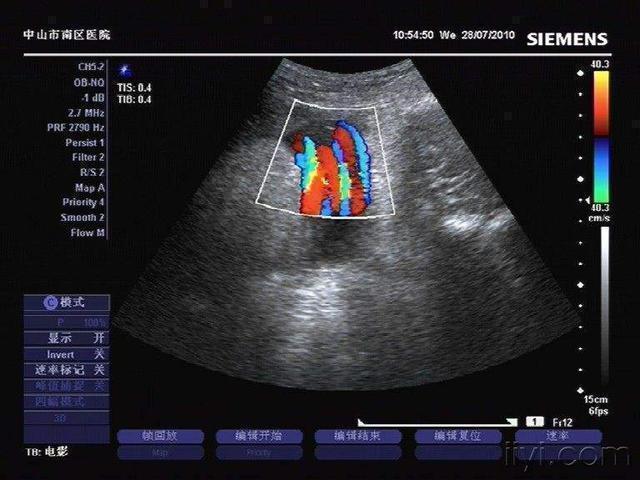

怀孕期间,全家人一直都很紧张,生怕胎儿得不到好的照顾。何女士更是早早地就开始准备胎教,想让孩子赢在起跑线上。等进入待产期后,何女士怕发生意外,早早地就住进了医院。这天早上,何女士突然觉得腹中的孩子好像不会动了,她感觉有点不太对劲。想起产检时,胎儿有脐带绕颈的状况。于是赶紧和老公一起去找医生,等医生检查以后发现,胎儿胎心已经降到一分钟60次了,可能会有生命危险。所以,医生立刻启动剖宫产应急预案。等胎儿的头露出的那一刻,医生和护士都惊呆了。原来胎儿的脖子上足足缠绕着五圈的脐带,脸都被勒得发青了,幸好发现得及时。紧接着医生把脐带从宝宝脖子上慢慢地解下,宝宝总算脱离了生命危险。